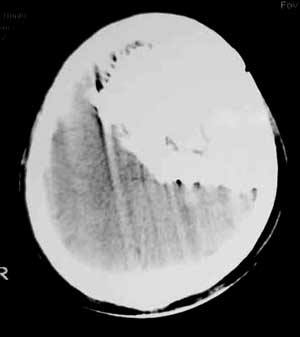

男性,60岁,反复癜痫40余年。

病理结果

骨软骨瘤